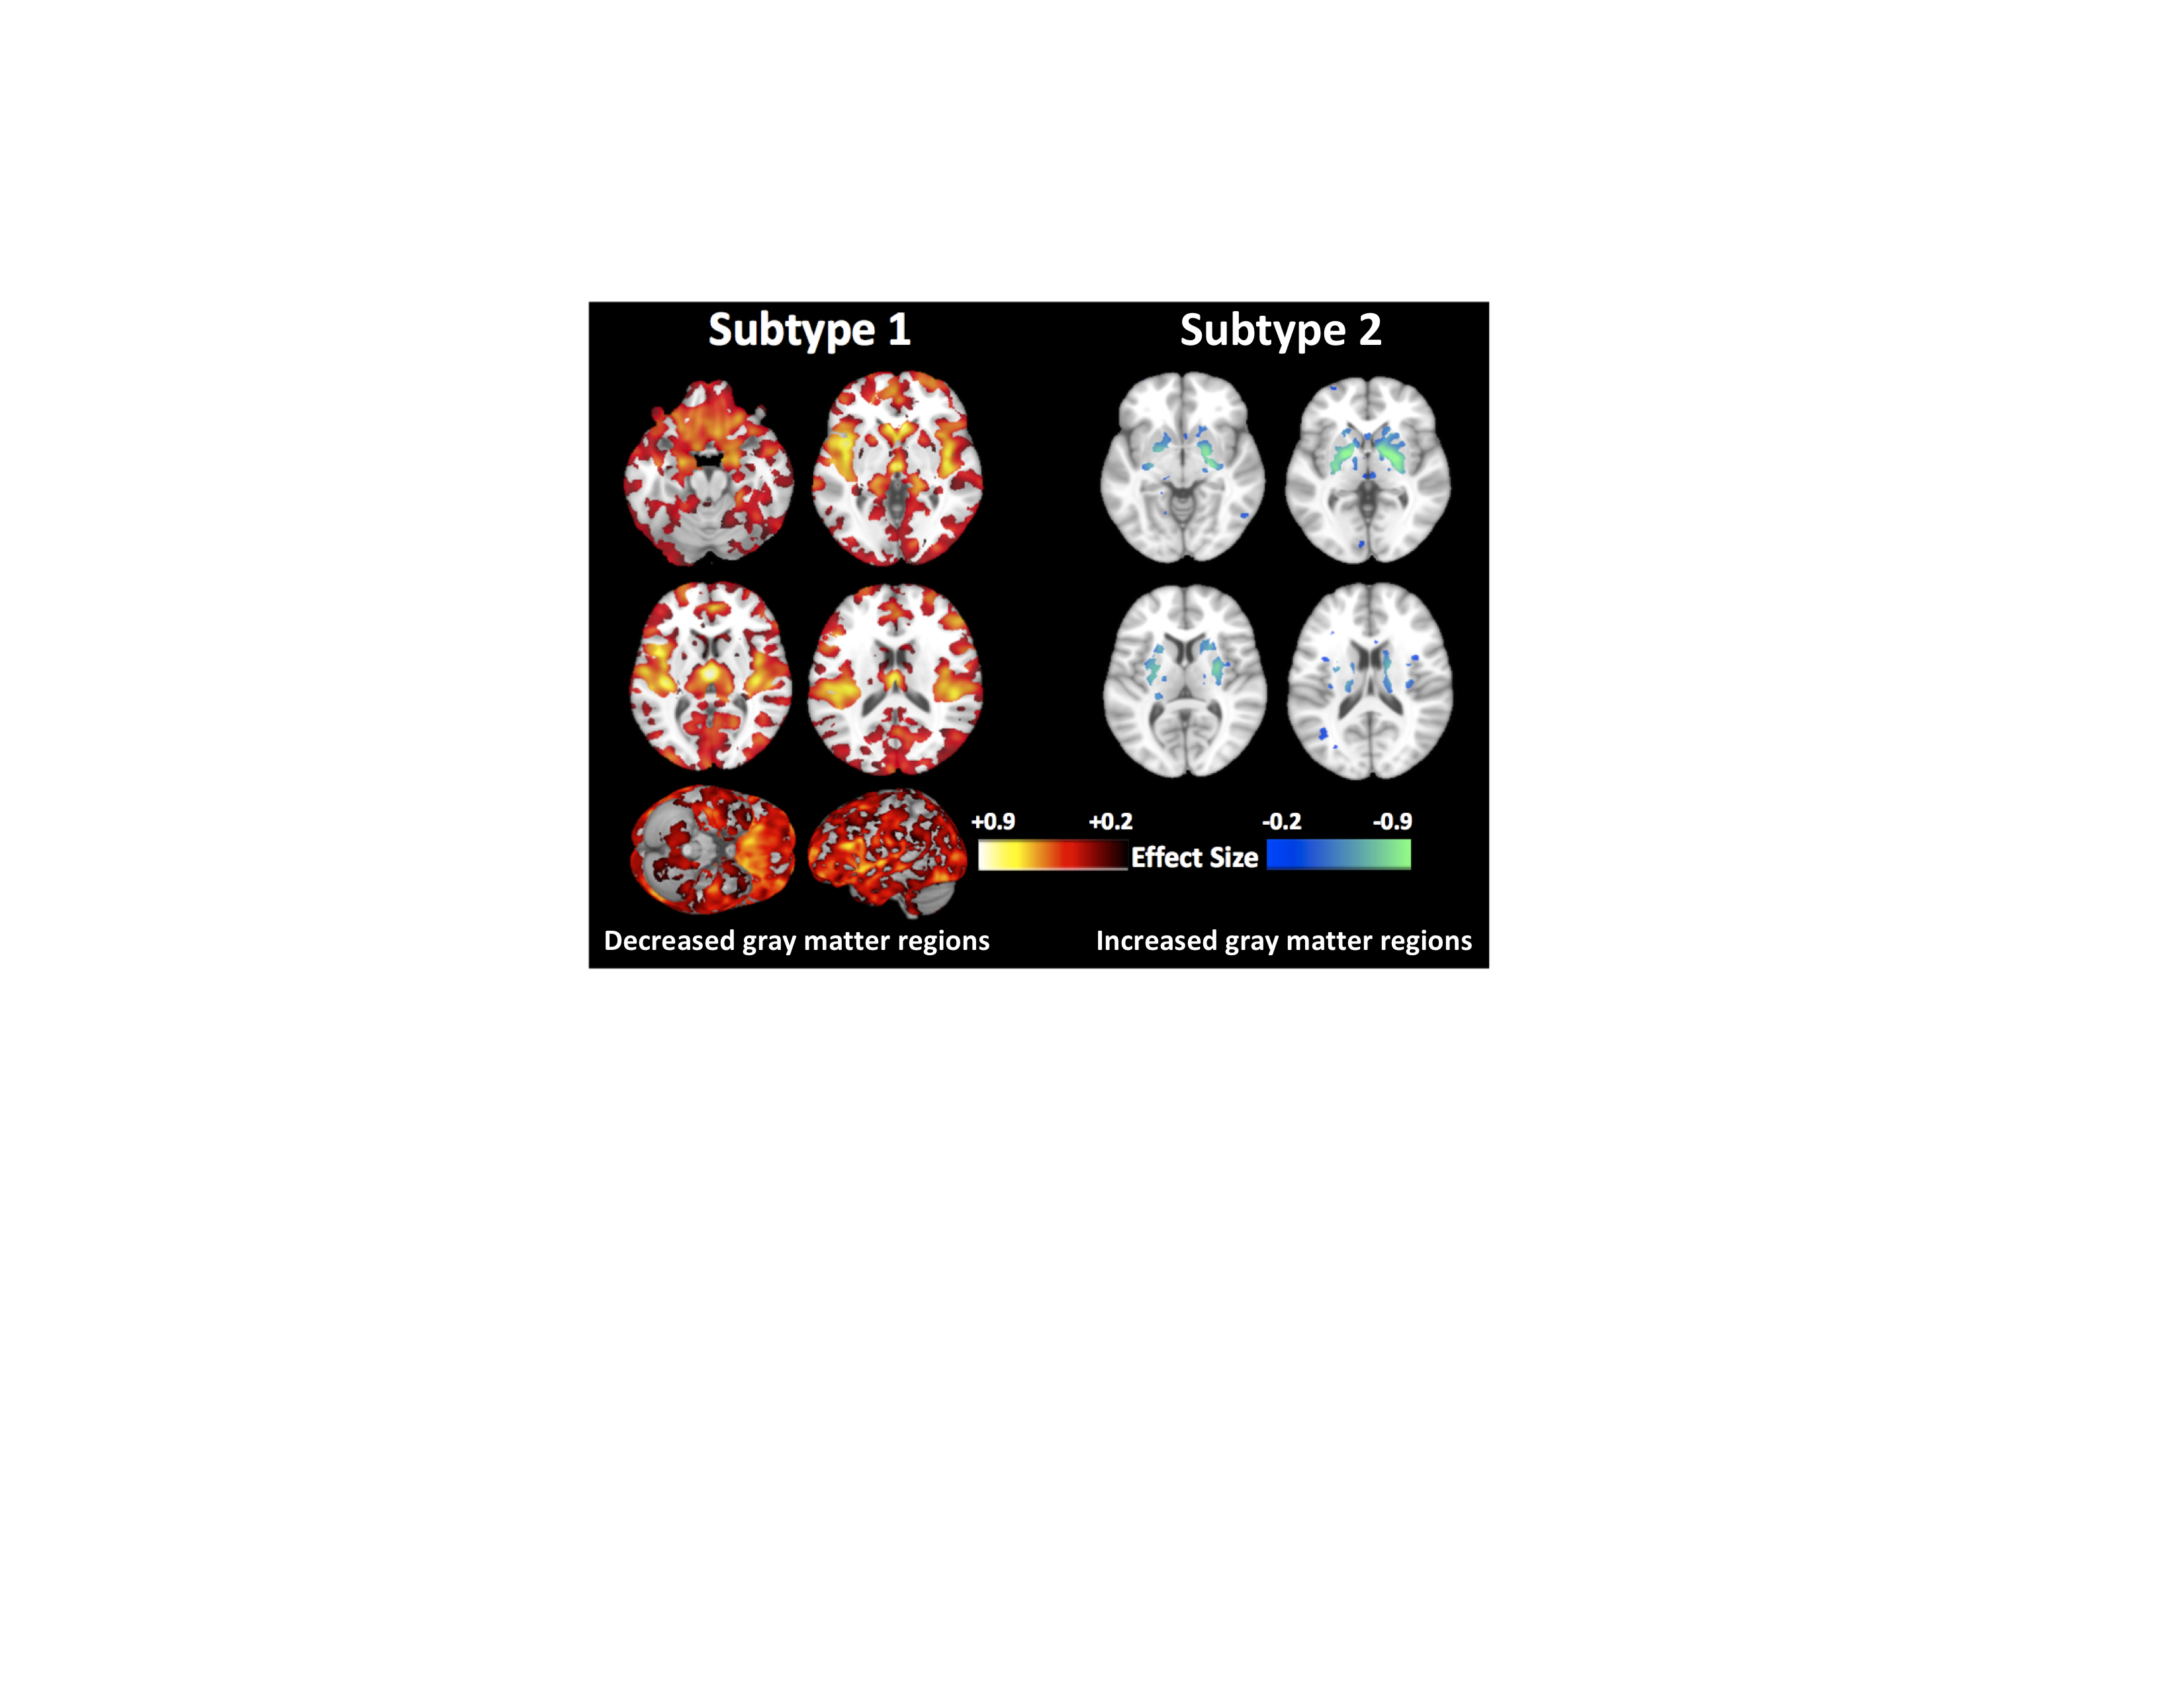

La contaminación del aire provoca daños en zonas cerebrales vinculadas al Alzheimer

25/05/2020